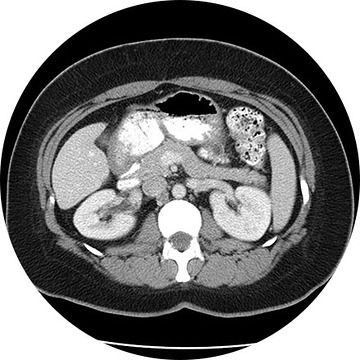

A CT (Computed Tomography) scan is an advanced type of X-ray exam. Multiple X-rays are taken rapidly from a number of different angles around the body and then arranged by a high-speed computer to produce a cross-sectional view. CT may be used to visualize internal organs, head, neck, spine or extremities.

For some CT scans, the radiologist injects intravenous contrast medium or dye to highlight certain tissues for closer examination. Certain patients may also be required to drink oral contrast as well. A CT scan helps differentiate between healthy and diseased tissue, making it possible to accurately diagnose many diseases in their early stages.